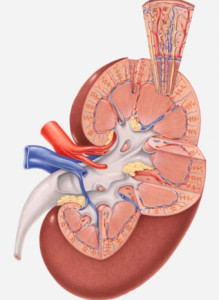

Az egyik leggyakoribb vese elváltozások - megalakult a ciszták. A ciszta perspektivikus formáció töltve folyadékkal. Meg lehet kívül található a vese, valamint a benne. Nem specifikus tünetek. Jelek a ciszták jelennek meg egy méretét megnövelné, hogy olyan mértékben, hogy a nyomást fejtünk ki a vese szövet vagy hajók. Ha mindkét vese alakult több mint öt ciszták vannak multiplexet diagnosztizáltak vese ciszták. Ez a diagnózis meg kell különböztetni a policisztás.

Különös betegség tünetei nem, emiatt lehet elég hosszú ideig ismeretlen személy, és gyakran kimutatható véletlenül. Ha a beteg tünetei a vese problémák, majd ecset méretét jelentős volt, általában több mint 5 cm. Úgy nyomja össze a pohár vagy vesemedence, ellátó erek a vese vérrel.

Ezek a módszerek segítenek elképzelni a vese, hogy meghatározzák a mérete, alakja, jobban megértjük a ciszták találhatók, hogy nagy nyomás fejtik a vesére.